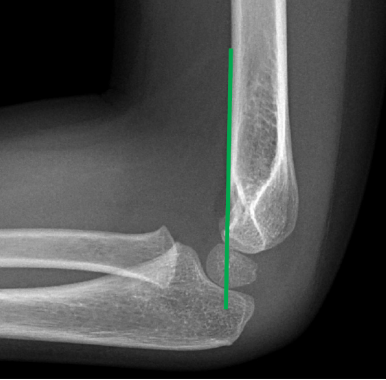

Det är avgörande för bedömningen att det finns en rak sidobild, d.v.s. där konturerna för den s.k. tårdroppen möts utan att överlappa. Oxynorm mixtur innan röntgen ökar chansen att få till korrekta projektioner.

Rak sidobild med linje utmed anteriora kortex som skär genom capitellum. Om linjen inte skär genom någon del av capitellum är det för mycket dorsalbockning för att acceptera konservativ behandling. |